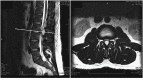

Second lumbar spine magnetic resonance imaging three months after the initial imaging. T2-weighted sequence shows a heterogeneous hyperintense cystic mass at the L3-L4 dorsal epidural space and the initial cystic mass at L2-3 level has resolved.

Post-operative T2 MRI sequence demonstrating decompressed lumbar spinal canal with total resection of the synovial cyst